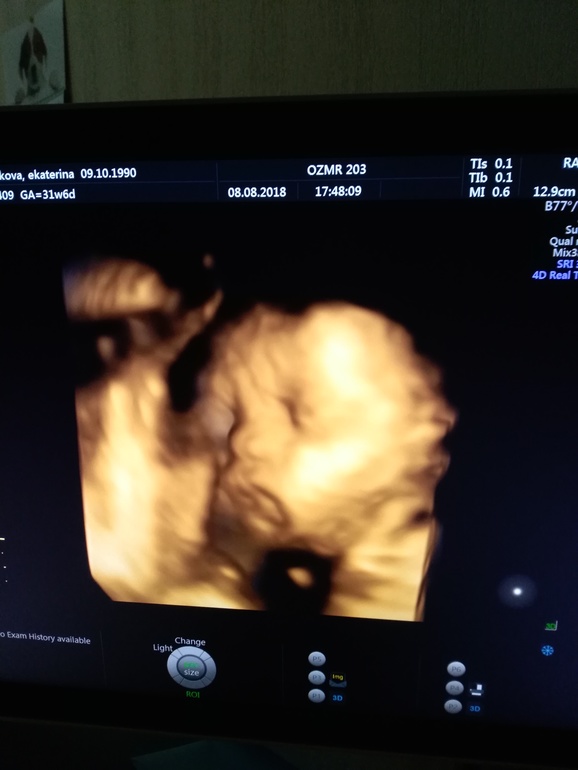

Первое практически фото моего чада

тут хмуримся

Вчера был последний скрининг. 2 кг, двойное обвитие сохраняется. Щёки у нас знатные. Ротик мой, а нос по моему свекрови.